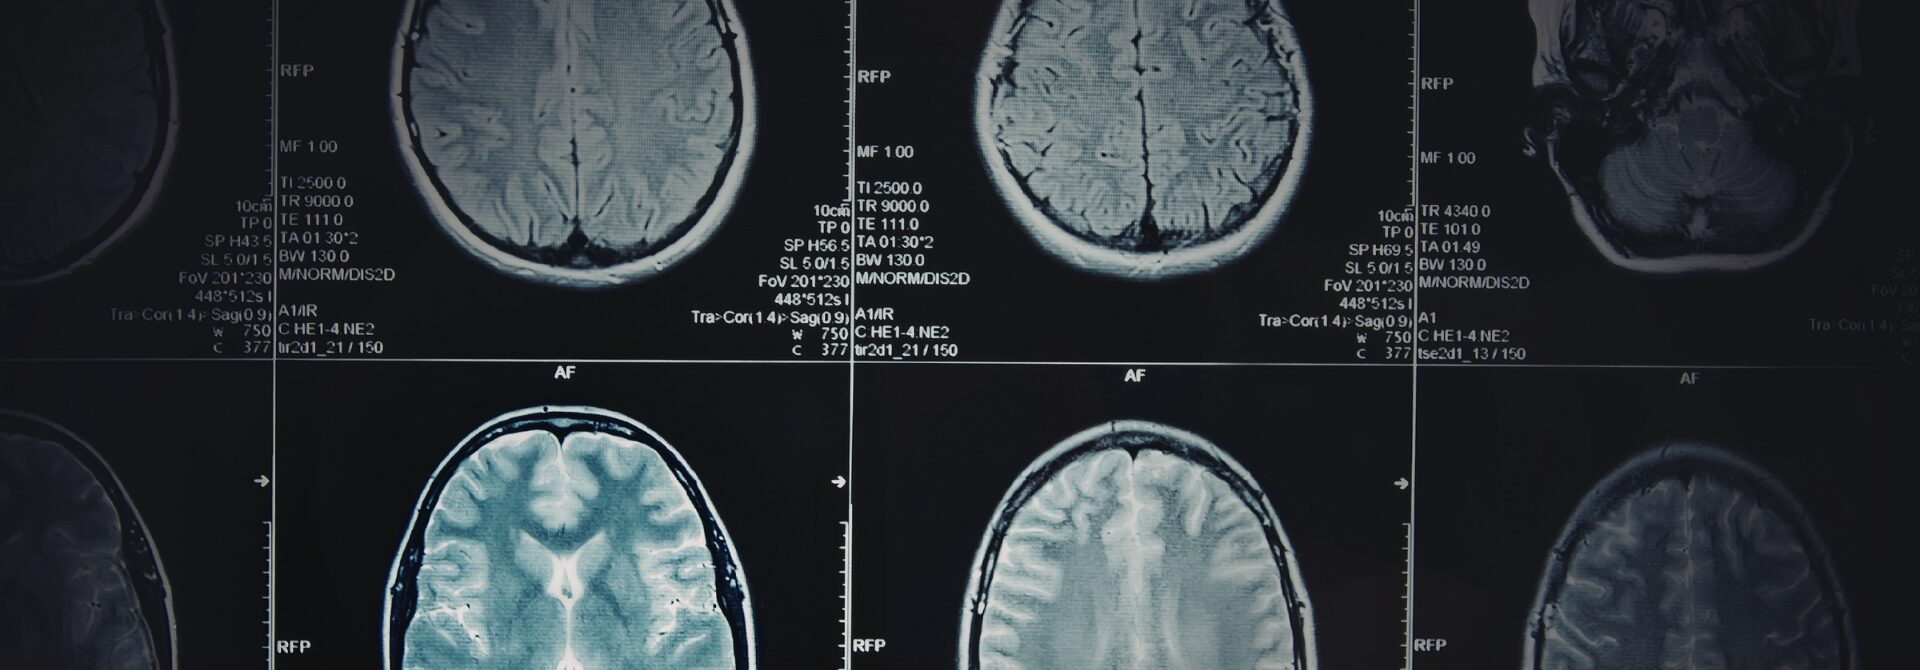

brain scans

Securing Traumatic Brain Injury Compensation

Brain injury claims are caused by medical negligence and can have life-changing consequences. Even the most minor trauma to the brain can result in paralysis, difficulty with speech and personality shifts. Brain injuries not only impact the individual but also their loved ones.